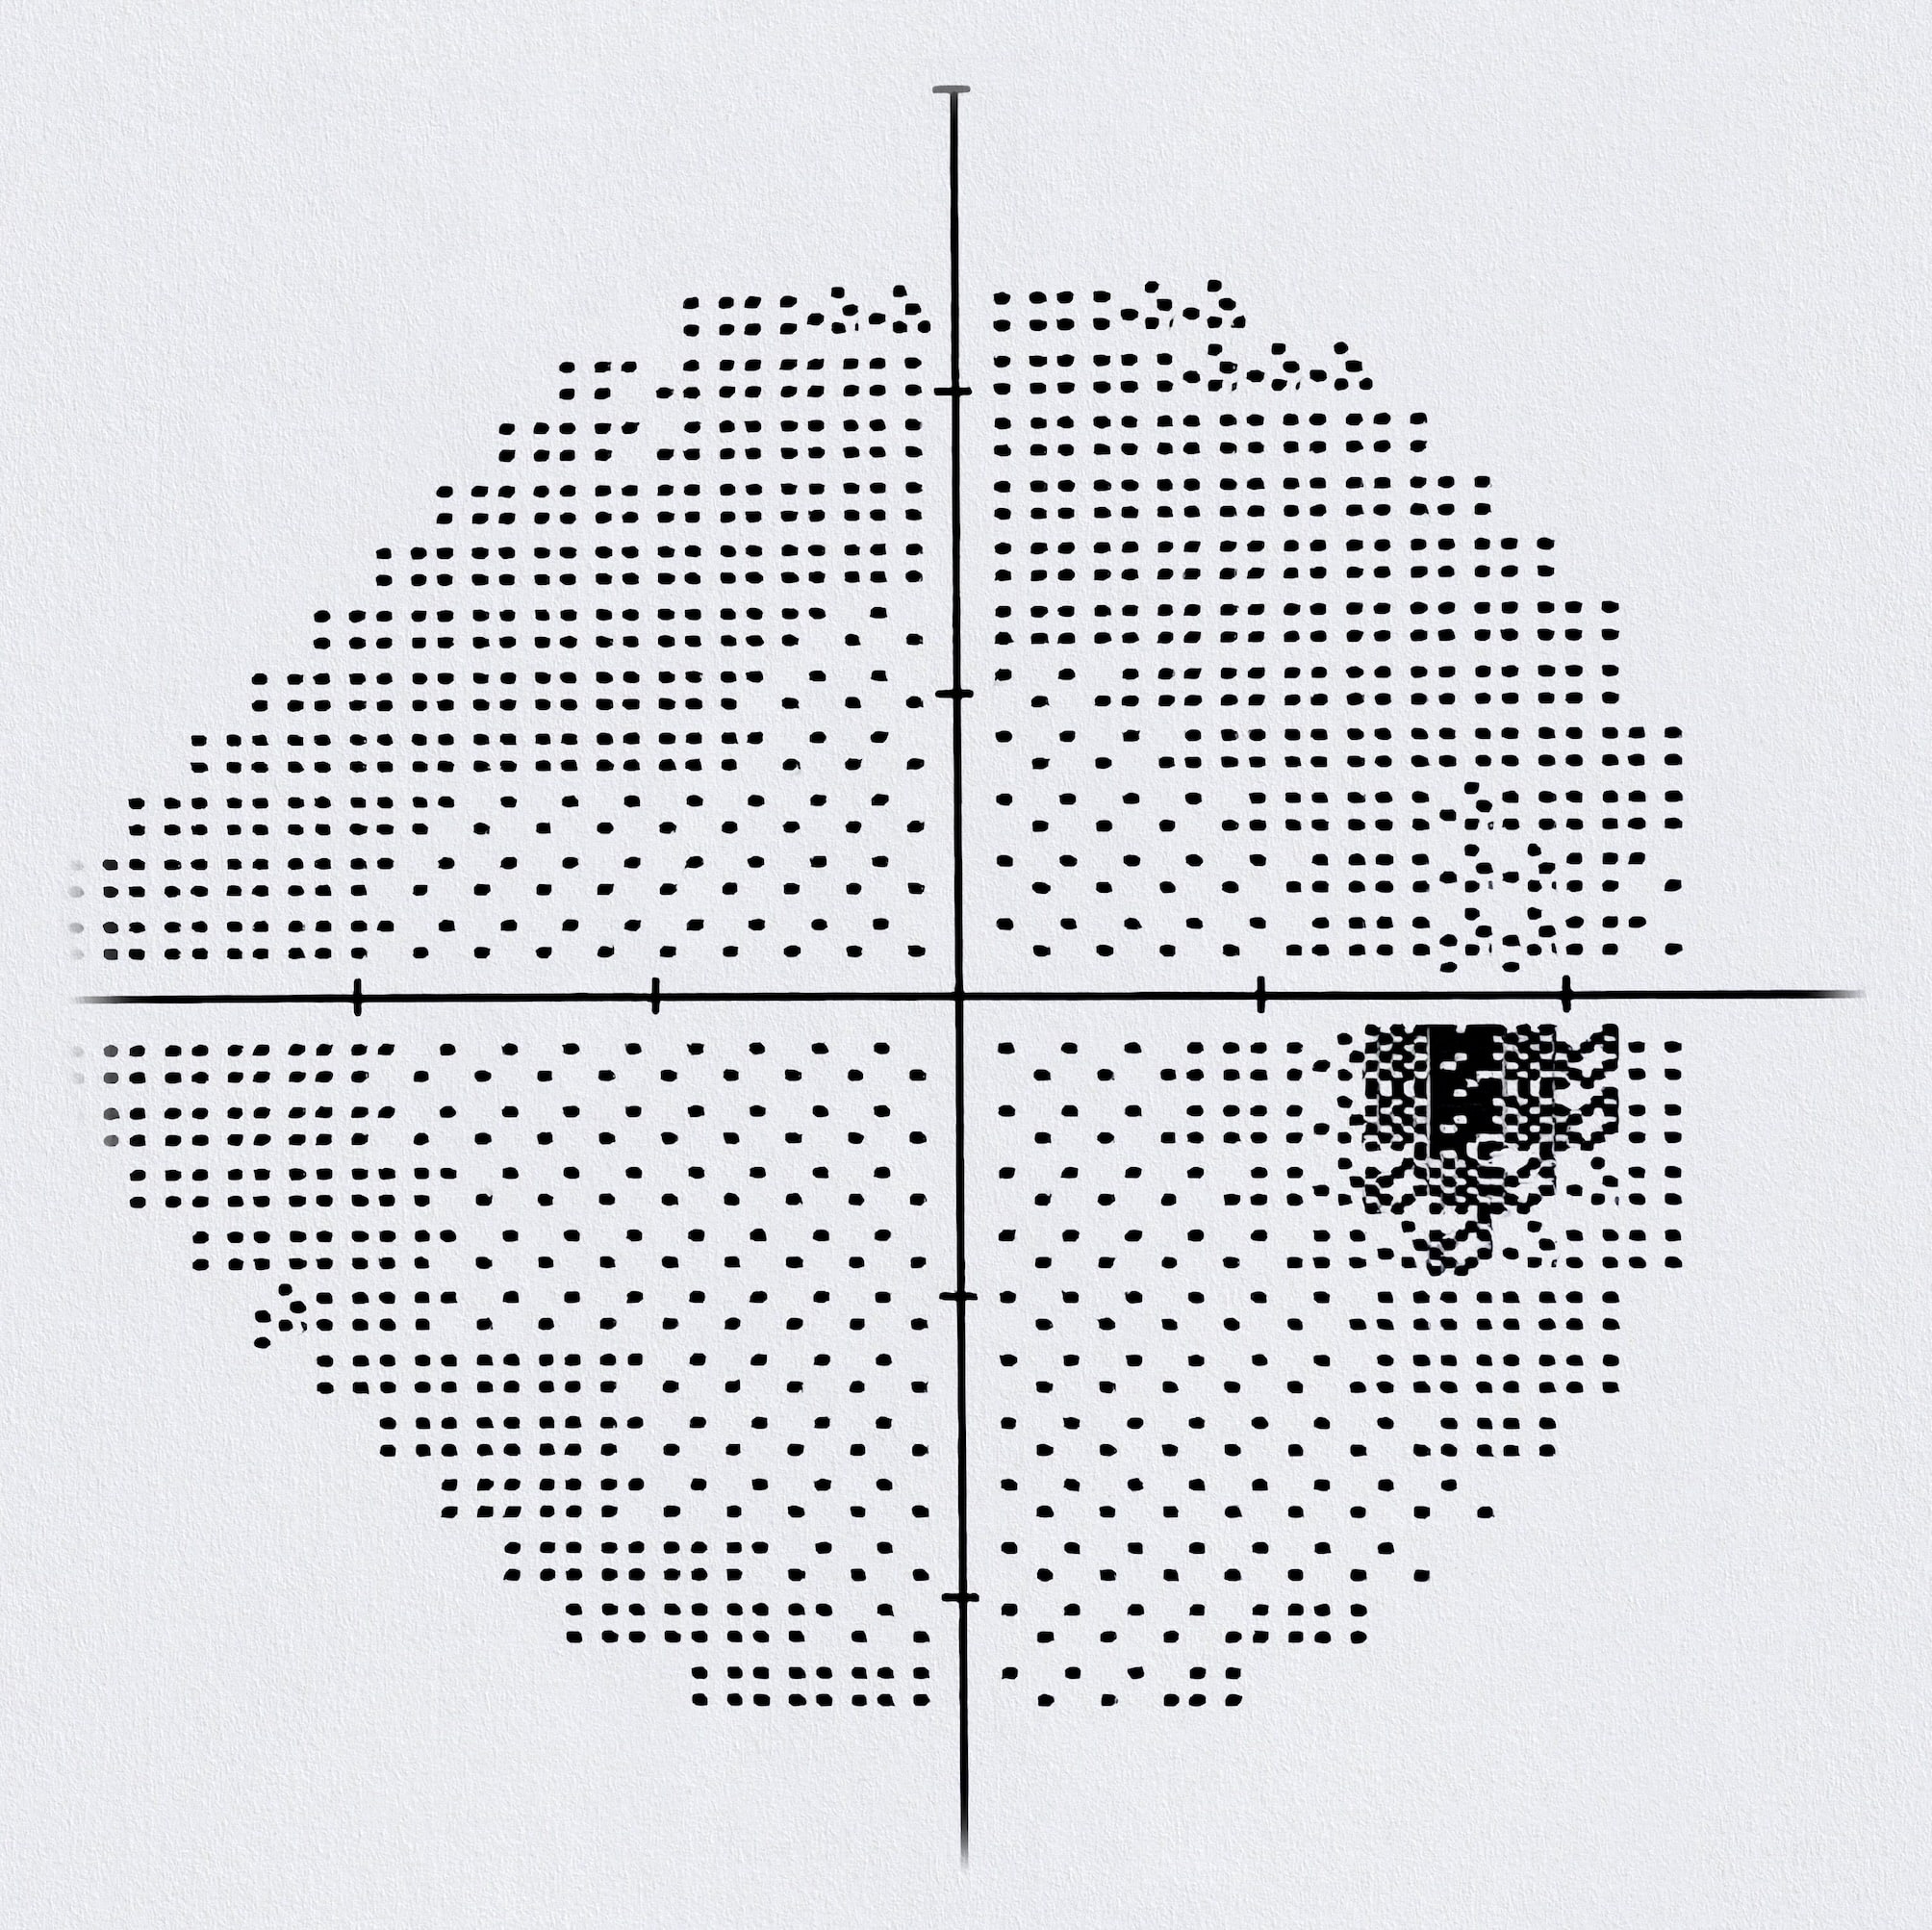

Les tests du champ de vision Pour un bon déroulement de l'examen du champ visuel, il est recommandé d'être bien installé. Pourquoi un examen du champ visuel est-il crucial ? C'est l'examen le plus important pour diagnostiquer et suivre un glaucome

Source: paobanerwlv.pages.dev Examen de Champ Visuel à Paris Analyse Précise au Centre Paris Rétina Vision , L'examen du champ visuel consiste à cartographier l'espace environnant qu'une personne peut percevoir en regardant droit devant elle.Il est principalement indiqué lorsqu'on soupçonne un. Le champ visuel est réalisé œil par œil, avec une durée moyenne de 5 à 10 minutes par oeil

Source: fletportnsz.pages.dev Champs visuels automatisés Centre Ophtalmologique Louis Paufique , Faire pratiquer un champ visuel HUMPHREY 24-2 Sita-Fast Dans ce contexte, on peut constater une anomalie pouvant toucher un quart ou la moitié du champ visuel des deux yeux

Source: jdcraftptu.pages.dev Examen du champ visuel définition, cause, symptômes, traitement , L'examen du champ visuel consiste à cartographier l'espace environnant qu'une personne peut percevoir en regardant droit devant elle.Il est principalement indiqué lorsqu'on soupçonne un. Prendre un RdV avec un Ophtalmologue pour un Champ visuel à Paris